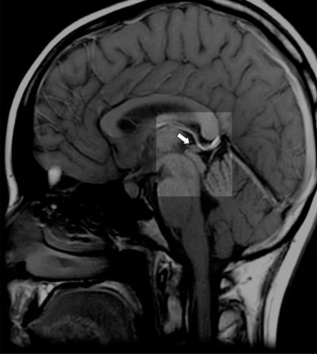

Deep in the geometric center of your brain, behind your eyes and between your ears, sits a pinecone-shaped gland no larger than a pea. The ancients called it the seat of the soul. Descartes declared it the principal seat of consciousness. Modern science calls it an endocrine gland.

The pineal gland is unique among brain structures — it exists outside the blood-brain barrier, making it exquisitely sensitive to everything flowing through your bloodstream. Under a microscope, pineal tissue contains rod-shaped, light-sensitive cells nearly identical to those in your retinas. Evolution didn't place retinal cells in the center of your skull by accident.

Here's what conventional medicine knows but rarely discusses: The pineal gland calcifies more than any other tissue in the human body. By middle age, many people's pineal glands contain calcium deposits visible on MRI scans, forming what researchers call "brain sand" or corpora araceacea.

Q: How do I know if my pineal gland is calcified?

A: Most people's pineal glands show some degree of calcification by middle age. Signs include: disrupted sleep patterns, difficulty achieving deep sleep, loss of dream recall, feeling disconnected from intuition, circadian rhythm disturbances (jet lag sensitivity, shift work intolerance), and early aging signs. An MRI or CT scan can show calcification directly, though most doctors don't routinely check for it.